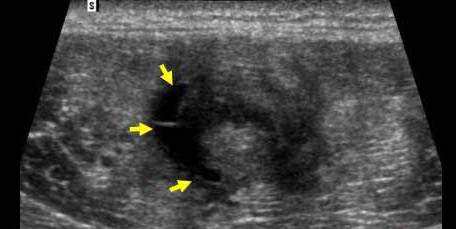

Stadiul III Rodineau – mica colectie lichidiana

Echivalentul stadiului al III-lea a lui Rodineau se caracterizeaza prin prezenta unei colectii hematice intra sau peri lezionale

Aceasta colectie poate avea o ecostructura lichida sau pseudo-solida, coresponzand unui hematom organizat

In acest caz, doppler-ul este interesant caci permite eliminarea unei formatiuni tisulare vascularizate care constituie principalul diagnostic diferential.

Echivalentul stadiului al III-lea a lui Rodineau se caracterizeaza prin prezenta unei colectii hematice intra sau peri lezionale Aceasta colectie poate avea o ecostructura lichida sau pseudo-solida, coresponzand unui hematom organizat In acest caz, doppler-ul este interesant caci permite eliminarea unei formatiuni tisulare vascularizate care constituie principalul diagnostic diferential.